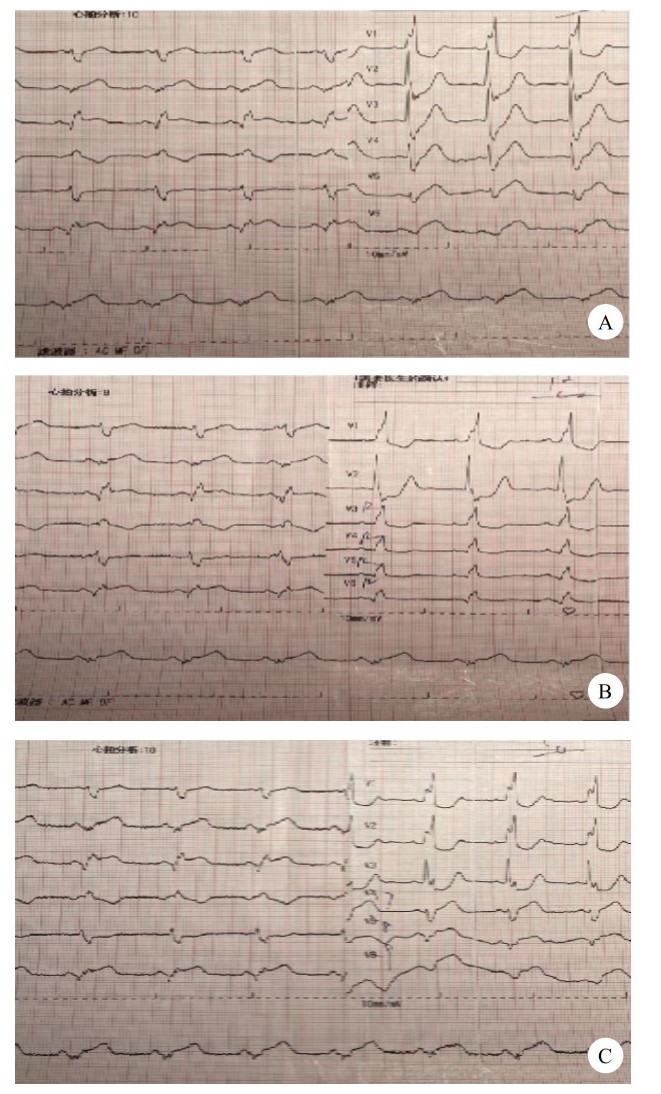

血常规:白细胞数9.46× 109/L,中性粒细胞绝对值8.57× 109/L,红细胞数3.96× 1012 L,血红蛋白118 g/L,血小板数266× 109/L;嗜酸粒细胞绝对值0.0× 109/L;嗜碱性粒细胞绝对值0.4× 109/L;凝血常规:正常范围;D- 二聚体:正常范围;肌钙蛋白:1.26 ng/mL;心肌酶:肌酸激酶890 U/L,肌酸激酶同工酶85 U/L。心脏彩超:节段性室壁运动异常;二尖瓣轻度反流;左室收缩及舒张功能减退(EF:42%);主动脉回声增强;主动脉瓣弹性减退。心电图提示:窦性心律,完全性右束支阻滞,Ⅱ、Ⅲ、avF ST段上抬,心电图见图 1。

| 图 1 患者急诊18导联心电图 |